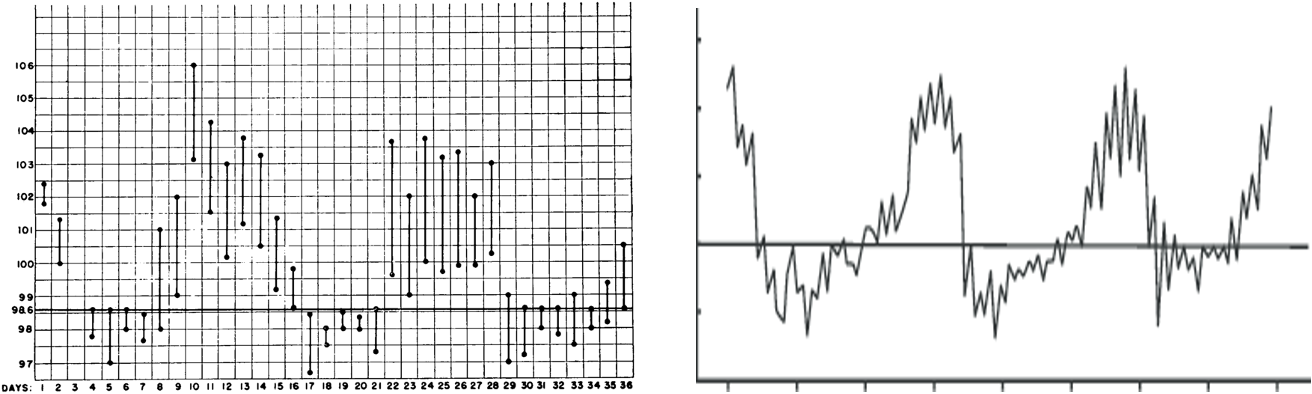

Pel-Ebstein Fever

- A cyclic pattern of fever, rarely seen in Hodgkin’s patients

- Fever present for a few days, then absent for a few days (cycle continues)